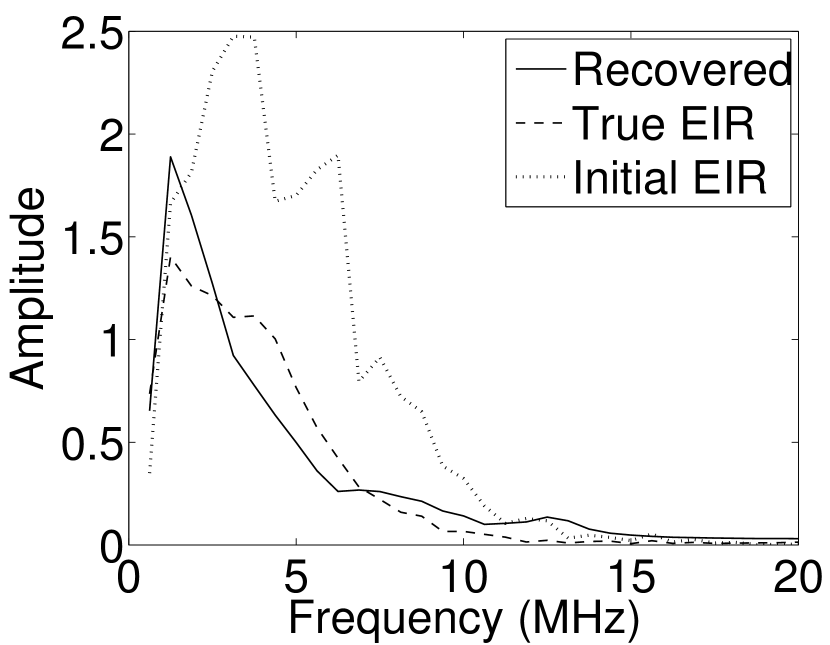

Images reconstructed by use of the VP algorithm with different values of the regularization parameter values are shown in Figure 8. The recovered EIRs and their corresponding Fourier spectra are shown in Figures 9 and 10, respectively. The RMSE values are computed and displayed together with the corresponding images. As expected, the images reconstructed with smaller values of contain higher noise levels, while images using larger possess a reduced noise level. However, larger values of also caused artifacts in the reconstructed images. The same observation can be made for the effect of the regularization parameter on the recovered EIR. One also observes that the reconstructed images and EIRs depend continuously on the regularization parameters and , i.e. small changes in the regularization parameters cause minor changes in the reconstructed images and EIRs.

VI Experimental validation